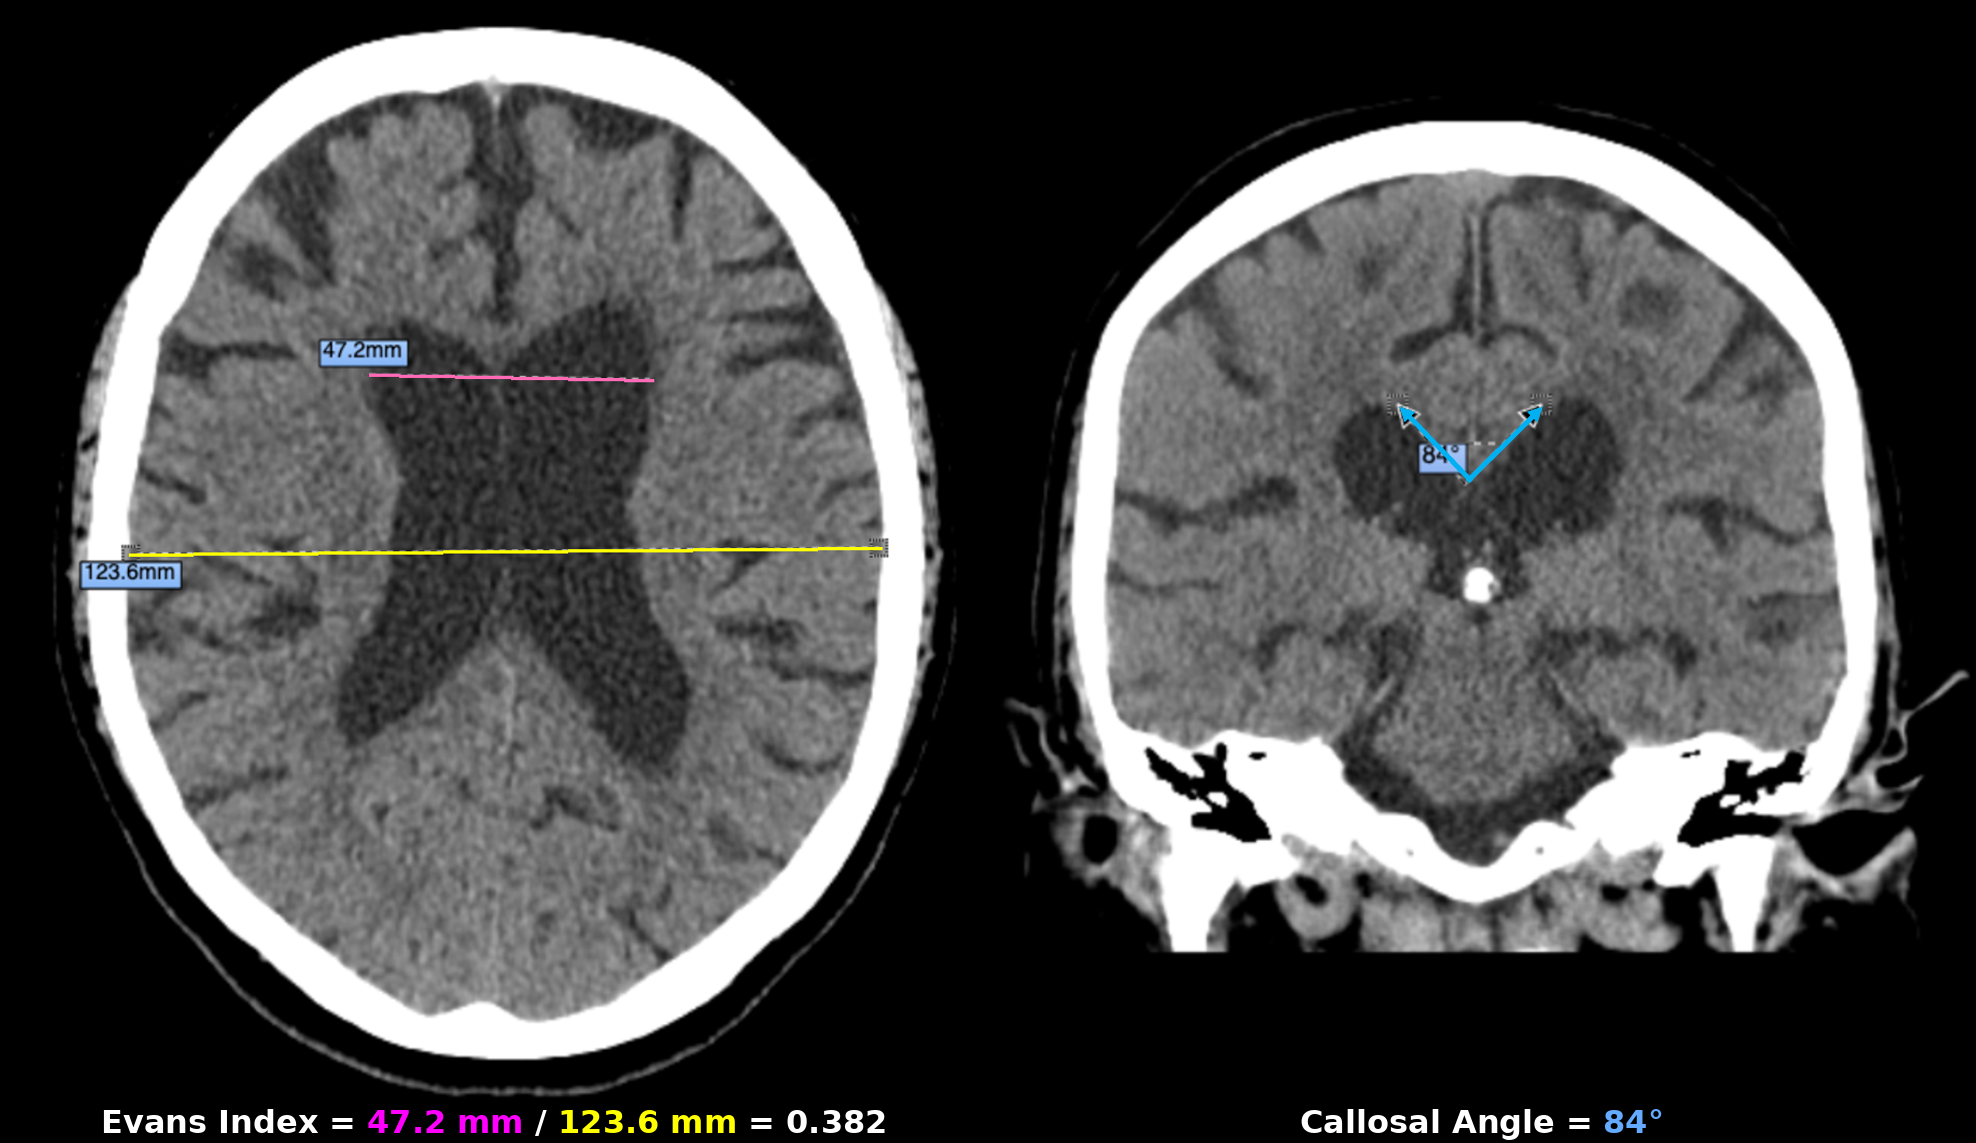

Tenecteplase for Treatment of Acute Ischemic Stroke in the Extended Time Window: A Review of Current Data

Sagarika Gopalkrishnan

Hana Danieli

Saad Hasan

Nchuofl2

BACKGROUND

The use of Tenecteplase (TNK) in the Extended Time Window (ETW) for Acute Ischemic Stroke (AIS) remains an ongoing debate. We aim to evaluate the current literature and data of TNK use for AIS in the ETW.

METHODS

Inclusion criteria for RCT of thrombolysis in the ETW:

• Study performed between 2018-2025

• Patients > 18 years of age

• AIS presenting within 4.5-24 hours from LKW or unknown/wake up stroke

• Pre-admission mRS < 2

Studies that did not meet these criteria were excluded from review.

From this, 3 RCTs were included in our review:

• TIMELESS

• TRACE 3

• CHABLIS-T II

DESIGN & RESULTS

Cnsf trial total enroll

Cnsf design 1

Design of all RCTs

Cnsf outcomes summarized

CONCLUSION

Better recanalization rates are seen with TNK in ETW, but may not be associated with improved functional outcomes at 90 days compared to medical management. Incidence of sICH also remains largely favorable, except in TRACE 3, which showed a higher incidence in the TNK group. There remains a need for more RCTs in this population.

Trial

LVO

EVT Access

Recanalization

Functional Outcome

sICH

TIMELESS

Yes

TNK group: ↑

No difference (mRS=3)

Similar

CHABLIS-T II

TRACE 3

No

N/A

TNK better (33% vs. 24.2%)

Increased in TNK group (3% vs 0.8%)